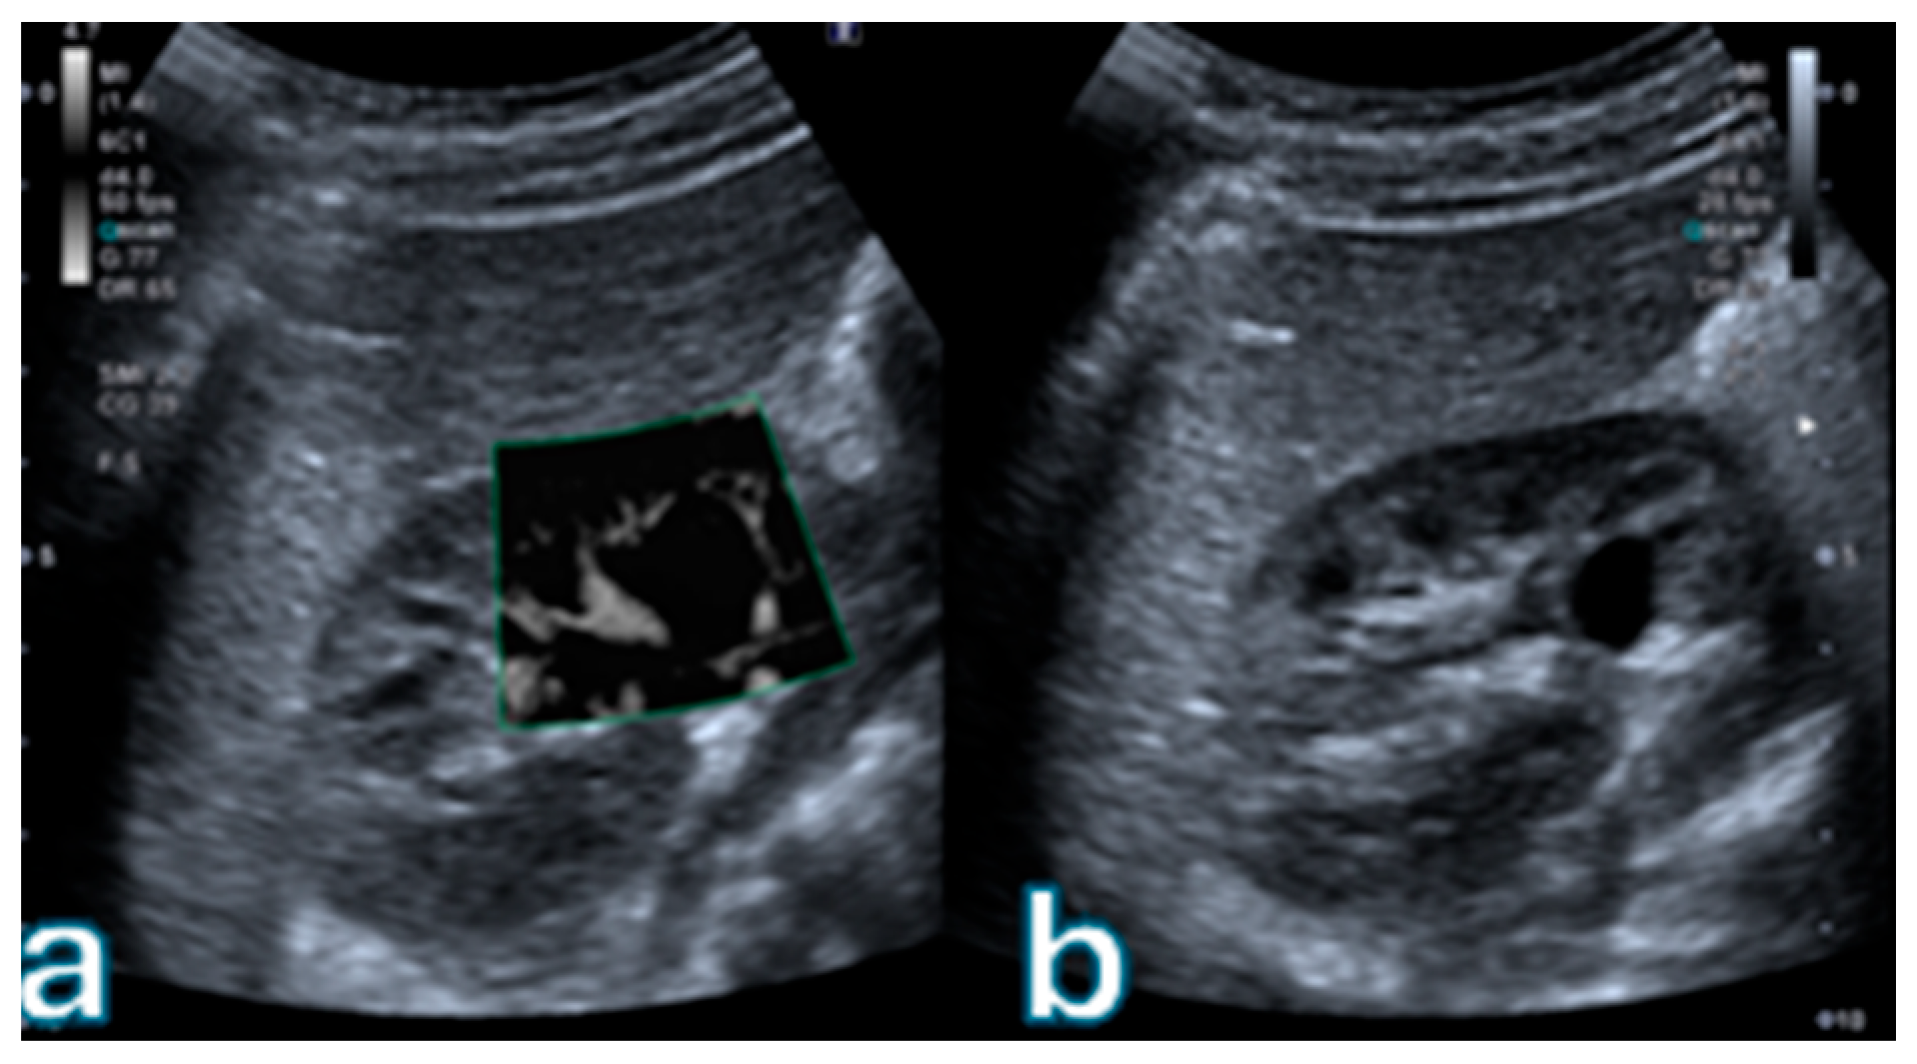

Figure 3 illustrates a representative Bosniak III cystic lesion with thickened, irregular septa. Superb Microvascular Imaging demonstrates discrete but definite microvascular signals within the septa, while CEUS confirms measurable septal enhancement in the absence of a solid mural nodule, consistent with an indeterminate high-risk cystic lesion.

Figure 3. Complex renal cyst classified as Bosniak III. (a) B-mode ultrasound shows a multiloculated cystic lesion with thick, irregular walls. (b) Superb Microvascular Imaging (SMI) reveals intense microvascular signals along the thickened septa and walls, indicating marked vascularization. (c) Contrast-enhanced ultrasound (CEUS) demonstrates clear enhancement of the thick walls without a solid mural nodule, consistent with a Bosniak III indeterminate high-risk cystic lesion.